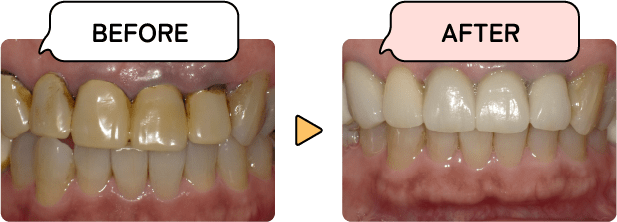

保険治療と自費治療の違いは、“費用”や“見た目の美しさ”だけではありません。ぜひ将来的な健康や美しさ、長い目で考えた経済性を考慮してお選びください。

保険治療

金属は強度があり保険適用のため安価ですが膨張収縮するので隙間が生じやすいためむし歯の再発や、金属イオンによるアレルギーを引き起こすリスクがあります。プラスチックは金属より見た目は良いですが、再現できるのは単色のため違和感がでやすく、強度がないというデメリットがあります。

自費治療

自費治療のため保険治療より高額になりますが、セラミックは微妙な色調の再現が可能で、透明感のある美しい歯を得ることができます。金属を使用しないので、金属アレルギーの方にも有効です。材料や治療法にも制約がなく、治療の質は保険の場合よりも良くなる可能性が高まります。

保険適応であるレジン前装冠は金属の上にプラスチック樹脂を使用しているために変色しやすい特徴があります。

セラミックを使用して、透明感のある色に仕上げています。長期間使っても変色しにくいのが特徴です。

歯ぐきと歯の間の金属が見えて見た目の違和感があります。金属を長期間使っていると歯ぐきが黒ずむことがあります。

被せ物の内側に金属を使用しないので、長く使っても変色せず、歯ぐきがさがっても金属がみえません。